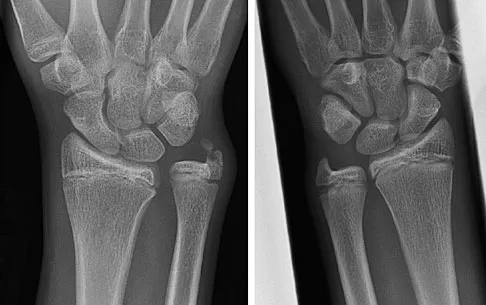

A 25-year-old student sustains the injury shown in Figures 13a through 13c after falling off a curb. Initial management should consist of

Explanation

The radiographs reveal a fracture entering the 4-5 intermetatarsal articulation, consistent with a zone 2 injury. This classically is also referred to as a Jones fracture. The history and radiographic findings indicate this is an acute fracture, which guides management. A zone 1 fracture enters the fifth tarsometatarsal joint, and a zone 3 fracture is a proximal diaphyseal fracture distal to the 4-5 articulation. Initial management is usually nonsurgical and consists of non-weight-bearing in a short leg cast. This method has been shown to result in a better healing rate compared to weight bearing as tolerated. Rosenberg GA, Sterra JJ: Treatment strategies for acute fractures and nonunions of the proximal fifth metatarsal. J Am Acad Orthop Surg 2000;8:332-338.